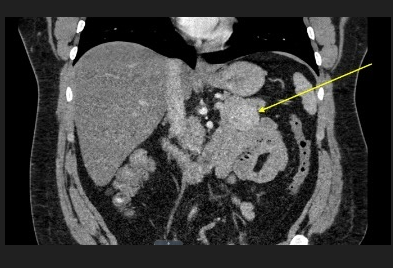

Figure 1: CT abdomen pelvis with and without contrast was ordered and revealed a 3.8x 4.0 cm solid enhancing mass arising from the pancreatic tail. There was no pancreatic ductal dilatation or atrophy. This may represent an insulinoma in the appropriate clinical setting.